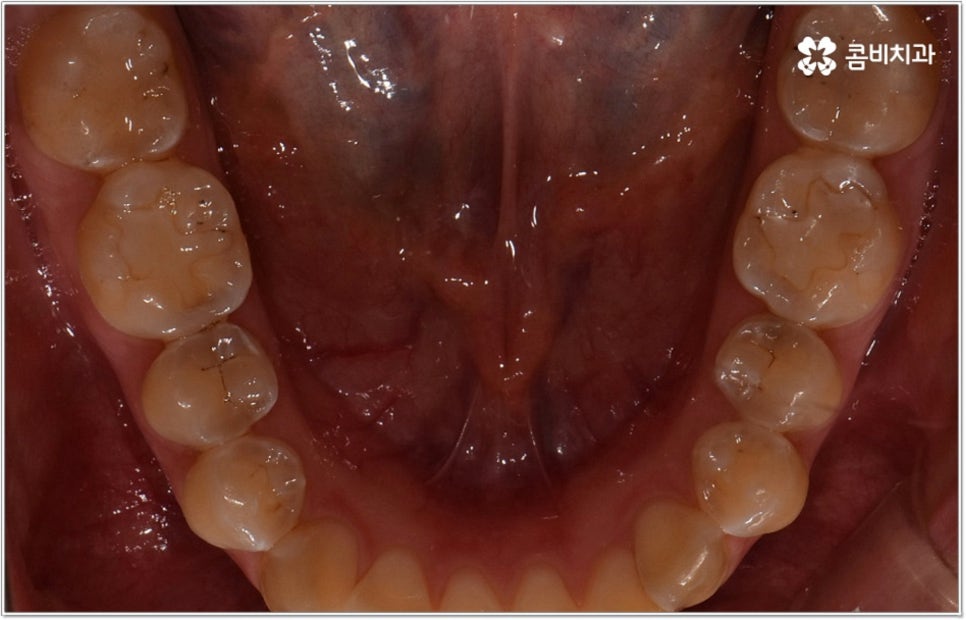

잘 아시다시피 교정이란 치아에 교정 장치 (브라켓) 를 부착하고 와이어에 교정력을 걸어 필요한 방향으로 치아를 이동시킴으로써 고른 치열과 올바른 교합을 가진 정상적인 구강 구조를 회복하는 치과 진료를 의미하는데요, 말씀드린 것처럼 부정교합에는 다양한 형태가 있고 또한 환자분들마다 심각한 정도가 모두 다르기 때문에 현 상태를 면밀하게 체크하고 맞춤 교정 치료 계획을 세우는 것이 무엇보다 중요하다고 할 수 있습니다. 즉 3D CT 와 같은 정밀 진단 장비를 갖추고 있는 치과에서 교정 관련 임상 경험이 풍부한 숙련된 의료진과 함께 치료를 진행하는 것이 필수적이라고 할 수 있어요. 전체 방향 및 세부 플랜을 세울 때 각 환자에 맞게 치아의 이동 속도에 무리가 가지 않도록 하기 위해서 연령이나 발달 상황, 진행 상황을 면밀하게 살펴보는 것이 필요하며 또한 구강 내 공간 유무 및 부정교합 정도에 따라 발치 또는 비발치치아교정 여부를 결정하게 될 거예요.

만약 치아가 이동할 범위를 계산해 봤을 때 공간이 충분하다면 굳이 치아를 뽑지 않고 비발치치아교정 과정으로 치료할 수 있어요. 제일 뒤에 있는 어금니를 더 후방으로 이동시키거나 치간 삭제, 악궁확장장치 등으로 치아 사이를 벌려서 이동 공간을 확보할 수 있으면 비발치치아교정 이 가능한 거예요. 이 때 부정교합이 심각하거나 악골이 치아에 비해 많이 작은 경우, 구조적인 원인을 개선할 필요성이 있는 경우 등 발치 교정을 하는 것이 꼭 필요한 케이스라면 치아를 뽑아주어야 하며, 환자분들의 상황에 따라 다르지만 보통은 소구치를 발치하는 경우가 많이 있습니다.